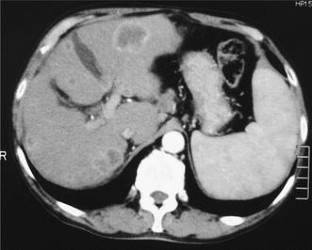

Primary biliary cirrhosis (PBC) is frequently complicated with hepatocellular carcinoma (HCC), but complication with combined hepatocellular and cholangiocellular carcinoma (cHCC-CC) or cholangiocellular carcinoma (CCC) has not been reported. Here, we describe a case of PBC in which cHCC-CC occurred. The patient was a 70-year-old man who had developed jaundice at 62 years old. He was diagnosed with PBC based on a liver biopsy and blood tests. In August 2006, blood tests showed elevated alpha-fetoprotein, and a liver tumor in the right lobe and a metastatic lymphadenopathy in the back near to the head of the pancreas were detected by abdominal contrast-enhanced CT. A 18F-fluorodeoxyglucose-PET scan showed accumulation of the tracer in the tumor and in a lymph node at the back of the pancreas. The tumor and lymph node were removed, and the tumor was diagnosed pathologically as cHCC-CC based on the presence of features of HCC and CCC. This case is the first to show that a patient with PBC can develop cHCC-CC. This is of interest, since cHCC-CC may originate in hepatic stem cells or hepatic precursor cells. This case also suggests that cHCC-CC should be included as a differential diagnosis for a liver tumor complicated with PBC.

Fig. 1